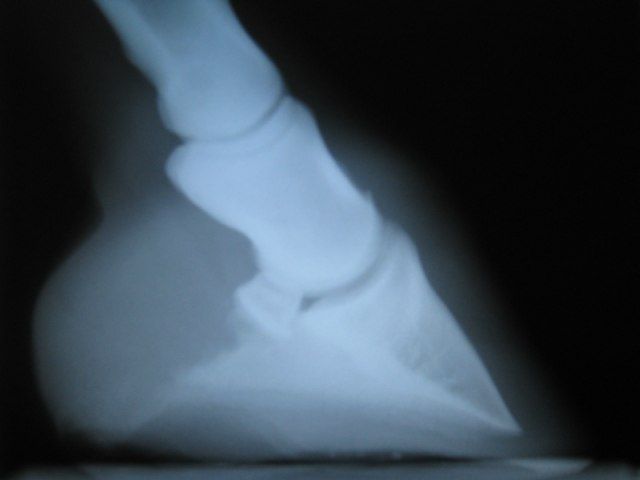

j'en ai donc profité pour faire faire une radio de l'antérieur droit qui me tracassait (avec son posé bizarre extérieur/intérieur)

la radio de profil est nikel, je la mettrai quand je l'aurai reçu avec le compte rendu

la 3 eme phalange est parfaitement aligné avec le reste

par contre peu de sole en pince mais après 3 mois de deferrage c'est normal et la sensibilité s'améliore de jours en jours!

j'ai reçu le compte rendu et donc la radio

on voit bien que y'a pas beaucoup d'épaisseur de sole en pince

Alors à votre avis, c'est normal pour un deferrage qui date d'il y a 4 mois?

Moi l'impression que me fait l'image, c'est certes qu'il n'y a pas beaucoup d'épaisseur en pince, mais surtout que P3 n'est pas bien horizontale... Et donc  avec le manque d'épaisseur, c'est peut-être ce qui explique la sensibilité puisque la pointe de P3 "appuie" sur la sole fine, au lieu que ce soit toute la surface de P3 qui supporte l'appui.

As-tu déjà essayé de faire légèrement descendre les talons au parage ? Peut-être que ton pareur te le proposera lui-même en voyant les radios ?

D'accord avec Pomme de pin et je rajouterai que selon moi (je le rappelle pas pro, pas taper moi :blush: ) les talons sont bien trop chassés vers l'avant et aplatis. Ce qui fait qu'on a l'impression que  la phalange est alignée à la paroi et que c'est bon alors que c'est pas bon. Effectivement la pointe de la phalange comme ça c'est pas bon.

le véto a trouvé l'alignement bon, la seule chose qu'il trouvait à redire c'était la finesse de la sole en pince.

Ouh là, la pareuse amateur de service pour notre bon Lann Bi pense aussi à baisser les talons !

C'est pas ce que j'appelle une phalange horizontale effectivement, et ça me conforte dans l'idée que je m'en faisait car au parage, on est limite à la rosée dès qu'on passe un léger coup de rape en pince.

Pour le moment, on a pas touché à la hauteur par crainte d'une boiterie, on y va très doucement... trop peut être.

J'attendais avec impatience cette radio que je réclamais à Salsa pour pas faire de bêtise, mais pour moi ça sonne comme une autorisation à descendre ;)